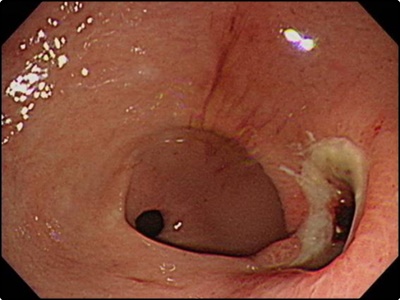

위산 역류의 현상인 속쓰림 또한 위암이 계속되고 있다는 위암 초기증상의 신호일 수 있습니다. 속쓰림의 경우 약을 섭취하면 치유가 빠른 편이지만 다시 쉽게 심해질 수 있습니다. 때문에 약을 섭취하고 난 차후에도 연쇄적인 속쓰림이 반복될 경우에는 증상을 신중하게 살펴야 합니다. 왜냐하면 단순 속쓰림이 아닐 수 있습니다. 간혹 이러한 속쓰림 증상은 위에 암세포가 증식하고 있다는 신호일 수 있으니까 명확한 검진이 필요합니다.

하지만 위암으로 발전하지 않게 하도록 연속적인 관리가 필요합니다. 때문에 정기적으로 꾸준히 위내시경 검사를 하는 것이 중요합니다. 때문에 위암을 미리 예방하기 위해서는 나트륨 과다섭취를 피하는 것이 좋습니다. 가능하면 위벽을 자극하지 않도록 해야만 합니다. 위가 자극을 받게되면 위궤양을 일으키고 암세포를 생성하게 됩니다.

조기 위암 환자의 경우 약 80% 가량은 위암 초기증상등의 증상을 느끼지 못했다고 합니다. 아무런 전조증상이 없다가 갑자기 위염인가 싶을 정도의 가벼운 속 쓰림 증세가 나타나게 됩니다. 이렇게 되면 이미 조기진단과 자가진단의 시기를 놓쳐 암을 키우는 경우가 많다고 합니다. 그러니 예방차원에서 정기적인 정기검진은 꼭 필요합니다.